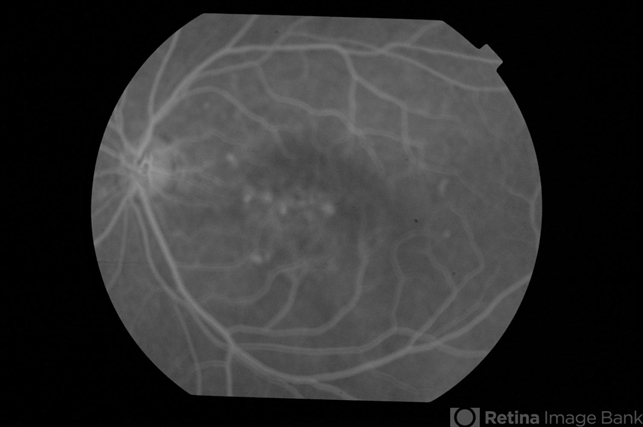

- CSCR subfoveal leak

- 52-year-old male with left eye CSCR of 6 months duration. Early phase fluorescein angiogram shows multiple leaks including a sub-foveal one. He was treated with PDT with complete resolution of fluid.